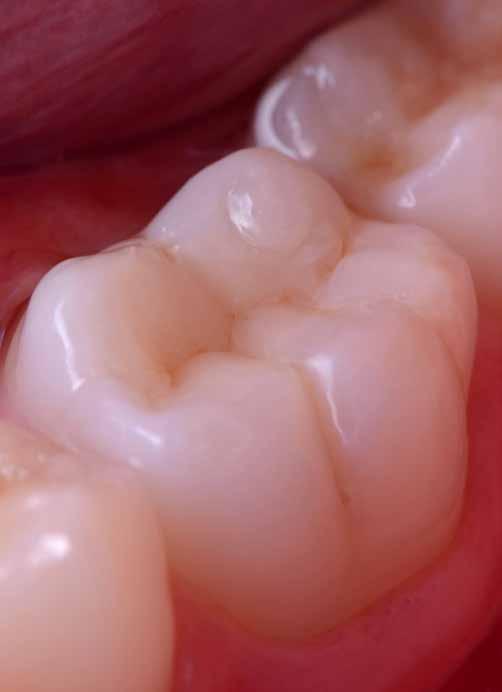

Az 53 éves hölgy páciens jobb felső 6-os fogában látható amalgámtömés cseréje volt a cél. A tömés mellett secunder caries és az amalgám következtében létrejött mesialis zárólécen áthaladó repedés, továbbá mesialis caries figyelhető meg (1. ábra). El kellett kerülni, hogy a tömés kifúrásakor az amalgámtörmelék a páciens szájába kerüljön, esetleg ebből valamennyit lenyeljen, a kezelés első lépésként kofferdám izoláció került fel a jobb felső kvadránsba (2. ábra). A kapocs a 1.7 fogra került, ezzel kényelmesen helyet teremtett a későbbiekben felkerülő matricarendszernek. Az egyszerre több fog izolálása lehetővé teszi, hogy a szomszédos fogak referenciául szolgáljanak a restauráció felépítése közben.

A régi amalgámtömés eltávolítását követően caries indikátor segítette a carieses laesio megfelelő kitisztítását a pulpa expozíciója nélkül. Ezután kerülhetett sor az ideális üregdesign kialakítására, továbbá a zománcszélek finírozására (3. ábra) Az approximális box megnyitása során az alátámasztatlan zománcprizmák eltávolításra kerültek, ezzel is csökkentve a secunder caries képződés veszélyét. Az így kialakuló forma elősegíti a matrica megfelelő adaptációját, végül pedig az approximális box határainak a hozzáférhetőségét, így finírozás során ez jobban kontrollálható és polírozható.